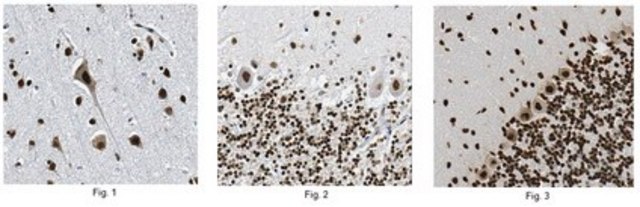

Immunohistochemistry Analysis: A 1:2,000 dilution from a representative lot detected Tdp43 in human frontal lobe, human cerebellum, and rat cerebellum tissue.